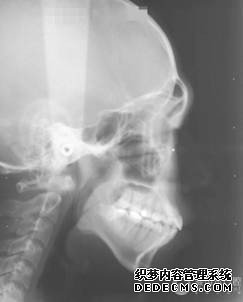

全景机侧位片

临床诊断:通过3D数字化全景机的拍片检查,患者上下牙排列拥挤,前牙受挤压向内歪斜,咬合关系异常,唇形尚可,颞下颌关节检查未见异常,无蛀牙、牙周疾病症状。经过和患者商量,选定自锁托槽矫正方案,调整牙间隙,恢复牙齿的正常排列,实现正常的咬合关系。